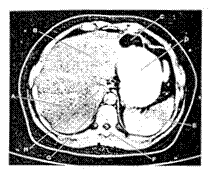

- Irisan Axial 1

Irisan axial 1 untuk memperlihatkan bagian atas liver. Liver dibagi menjadi dua lobus, lobus kanan dan lobus kiri.

ct scan perut

Gambar 2.4 : Irisan Axial 1 (Bontrager, 2001)

Keterangan :

A. Lobus kanan liver

B. Lobus kiri liver

C. Lambung

D. Lambung (fundus dan bagian atas daerah lambung)

E. Spleen

F. Vertebre Thoracal 10 dan Vertebre Thoracal 11

G. Aorta abdominal

H. Vena Cava Inferior